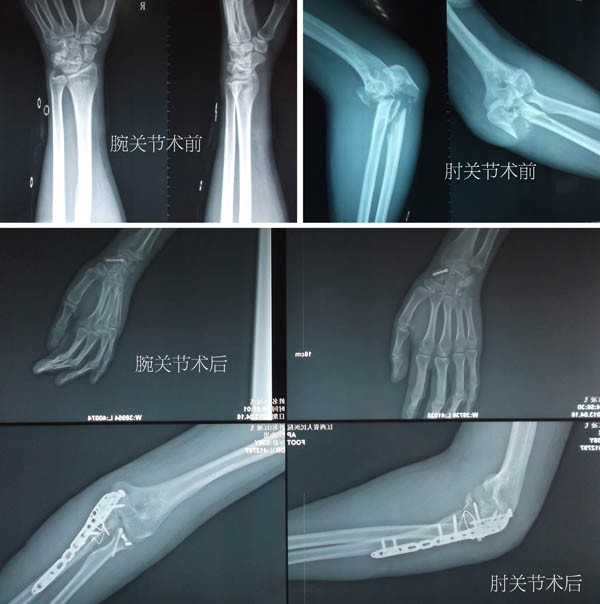

术后肢体功能图

腕肘关节

对于粉碎的桡骨头,常因难以复位固定或术后骨折坏死不愈合而予以切除,或使用昂贵的人工桡骨头进行置换。当手术中发现患者断离并分裂为两半的桡骨头碎块上均有部分关节囊附着后,董谢平不放过任何一个让患者受益的机会,耐心细致地进行了复位和小螺钉固定,直至关节面完全平整。但攻克桡骨头骨折只是万里长征的第一步,粉碎的尺骨冠突要与同样粉碎的尺骨鹰嘴完全复位,并共同复位于粉碎的尺骨上干骺端,而且要维持固定住这些碎骨片,其难度可想而知,即使在肘关节前方做辅助切口也难以实现。但长于微创技艺的董谢平主任为将病人损伤减少至最低,坚持只用一个切口完成了整个肘关节的复位固定术。经过将近4个小时的努力,患者恐怖的肘关节恢复了其原有的解剖关系,手术取得了惊人的成效。

解除了肘关节的恐怖现象后,董谢平着手逐一进行进行腕舟骨和跟骨的复位内固定。骨折的微创治疗是董谢平主任的拿手戏,与其讲董谢平主任水平高一些,还不如说他更认真负责一些。他以娴熟的手法复位骨折后,在进针点皮肤处戳一小切口,并在C形臂X线机的监视下经皮钻入细钢针,再沿细钢针拧入空心螺丝钉,完成了损伤小、花费少、恢复快的舟骨和跟骨骨折微创复位内固定术。